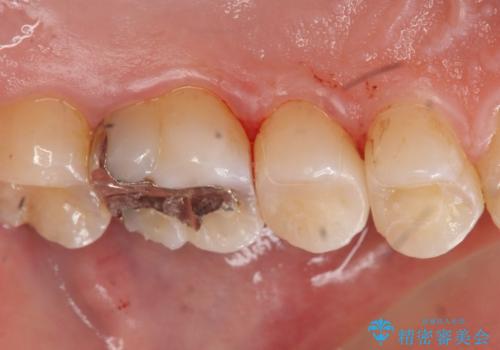

コンタクトカリエスの治療

- 虫歯の検査のために来院された患者さまです。

レントゲンで診査したら、歯と歯の間に虫歯(コンタクトカリエス)が見られたので

e-maxインレーで治療を行いました。